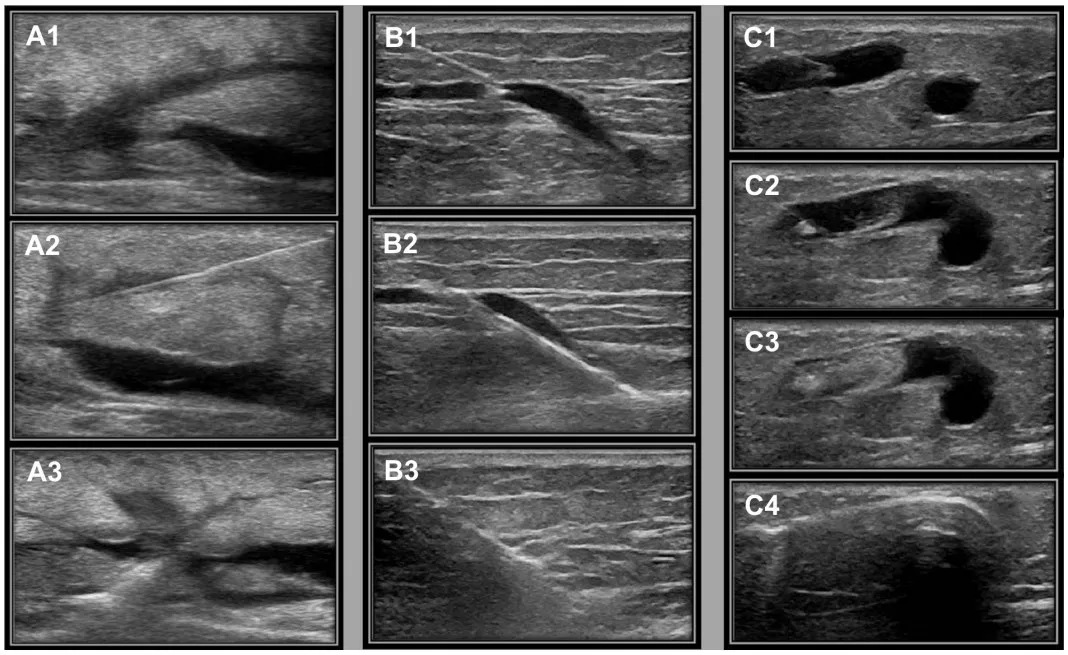

连续的双功多普勒图像显示病理性穿支静脉经三种方式治疗。A1-A3,激光消融;(B1 ~ B3) Seldinger技术用于射频消融(RFA);可见(C1 ~ C4)泡沫填充曲张静脉和病理性穿支静脉。